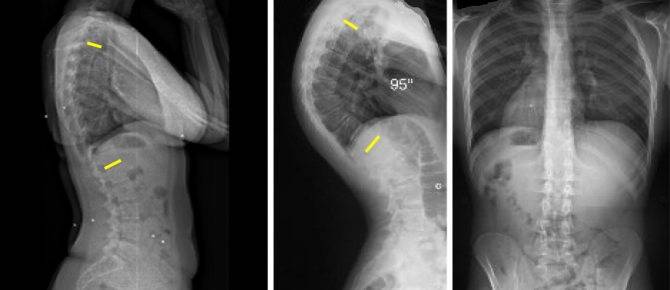

Так как причин патологии довольно много, обследоваться нужно сразу у нескольких специалистов, основными из которых являются вертебролог и невролог. Тщательное обследование поможет установить точный диагноз и подобрать максимально эффективное лечение. После первичного осмотра обязательно назначают рентгенографию или более современные методики – КТ и МРТ. Эти исследования позволяют выявить патологии позвоночного столба и прилегающих тканей, фиксируя малейшие отклонения от нормы.

На снимках отчетливо просматриваются малейшие изменения как в самом позвоночнике, так и в прилегающих тканях